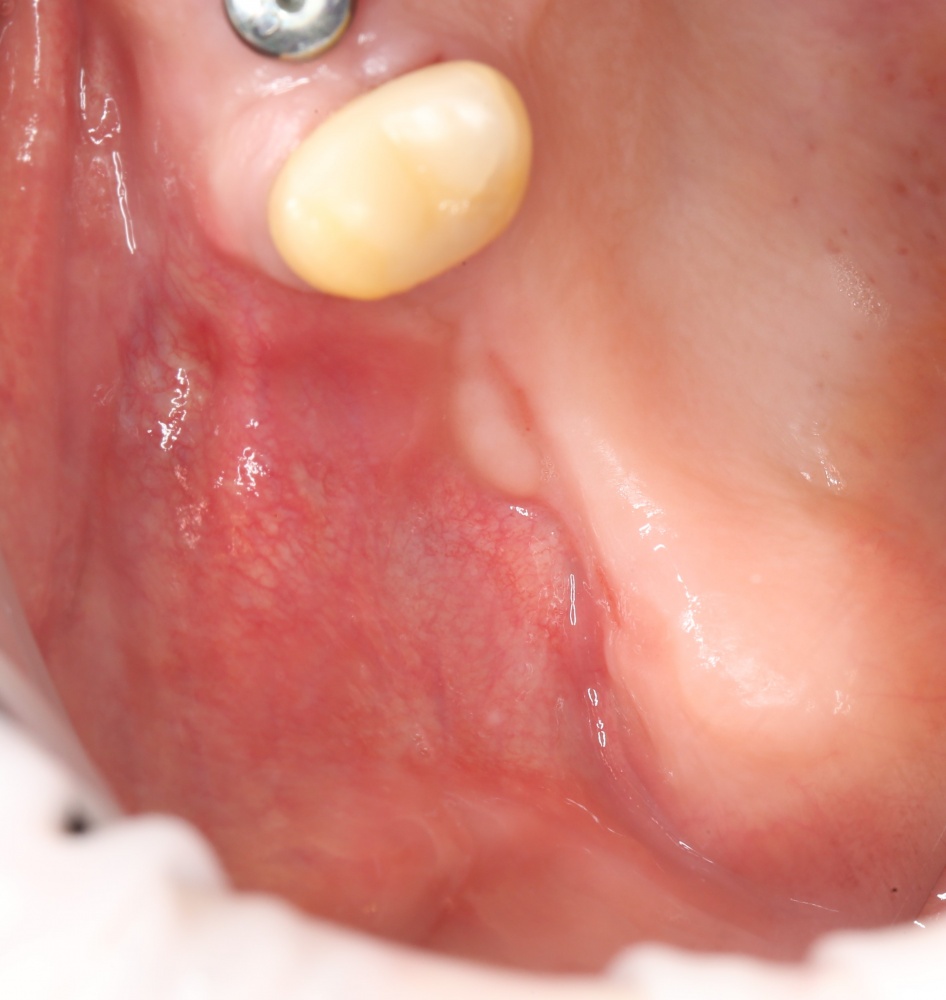

В данном клиническом случае есть одна проблема — почти полное отсутствие кератинизированной десны на вершине и с вестибулярной стороны альвеолярного гребня.

Если мы сделаем разрез по подвижной слизистой оболочке, его, скорее всего, потом будет очень легко свести и зашить. Но все, что легко сводится — так же легко расходится, а это значит, что герметизировать такую рану без дополнительных средств будет очень сложно, практически, невозможно.

Поэтому, несмотря на определенные неудобства, мы переносим наш разрез в пределы кератинизированной десны, пусть и очень небно.

Через 4 месяца область операции выглядит примерно так.

Через пару недель область, где мы провели уже две операции, выглядит примерно так: